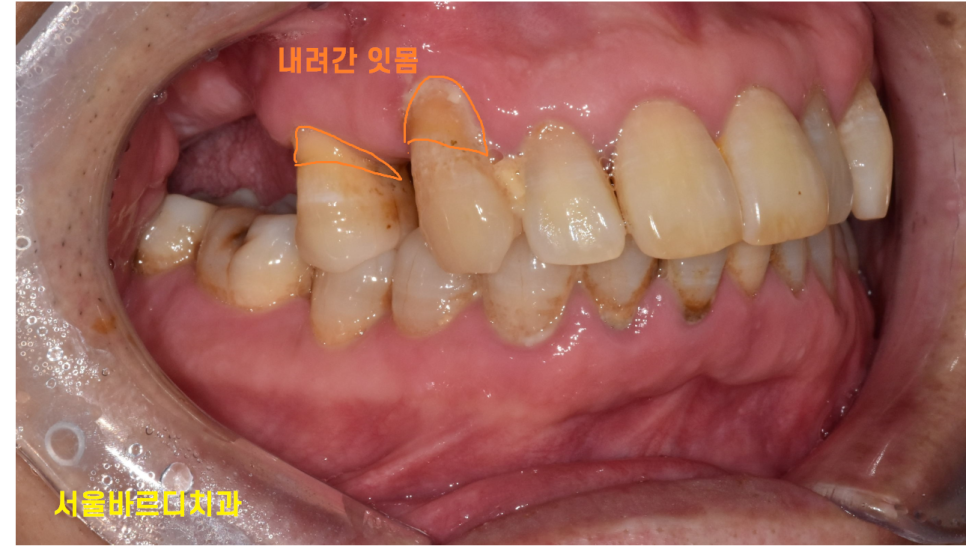

잇몸이 내려가면서

치아와 잇몸 사이 공간에 틈이 커지기도 하고요~

- 노화로 인한 잇몸 내려감

치아가 길어보이는 것도 잇몸이 내려가

치아 뿌리가 드러나면서 그렇습니다!!